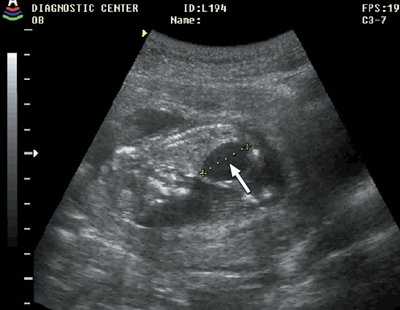

Рис. 8. Дефект межжелудочковой перегородки (стрелка), беременность 12 недель.